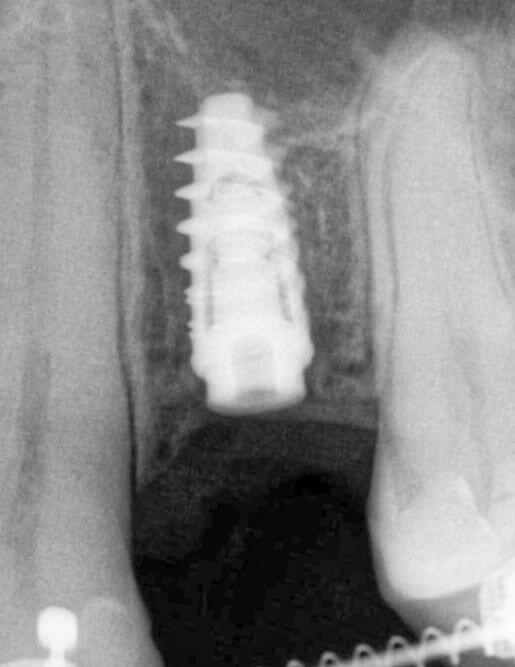

Більшість імплантів виготовляється з медичного титану. Він біосумісний, не викликає жодних реакцій та відмінно вростає в кістку щелепи.

Команда Космічної стоматології Драганчука - фанати якості та інноваційних технологій, тому обираємо імпланти кореня зуба з титану та його сплавів, зокрема Roxolid. Цей космічний сплав складається з титану та цирконію й має підвищену міцність (+30%). Це дозволяє використовувати імпланти особливо маленьких розмірів та уникнути додаткового нарощення кістки.

Команда Космічної стоматології Драганчука - фанати якості та інноваційних технологій, тому обираємо імпланти кореня зуба з титану та його сплавів, зокрема Roxolid. Цей космічний сплав складається з титану та цирконію й має підвищену міцність (+30%). Це дозволяє використовувати імпланти особливо маленьких розмірів та уникнути додаткового нарощування кістки.